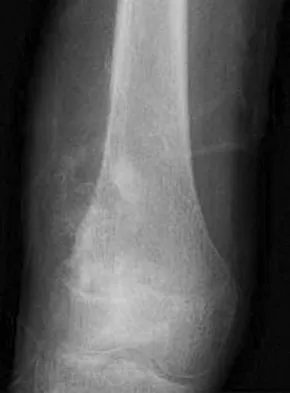

A 10-year-old boy with a history of retinoblastoma now reports right knee pain. AP and lateral radiographs are shown in Figures 3a and 3b. What is the most likely diagnosis?

Explanation

The radiographs show a bone-producing lesion in the femoral diaphysis. The radiographic appearance of small round cell tumors is more permeative with an elevated periosteum and no matrix production. The appearance of this lesion is most consistent with osteosarcoma. Patients who carry the Rb gene are predisposed to osteosarcoma. However, Ewing's sarcoma, primitive neuroectodermal tumor, and osteomyelitis can all occur in this location. Unni KK: Dahlin's Bone Tumors: General Aspects and Data on 11,087 Cases, ed 5. Philadelphia, PA, Lippincott-Raven, 1996, pp 143-160.